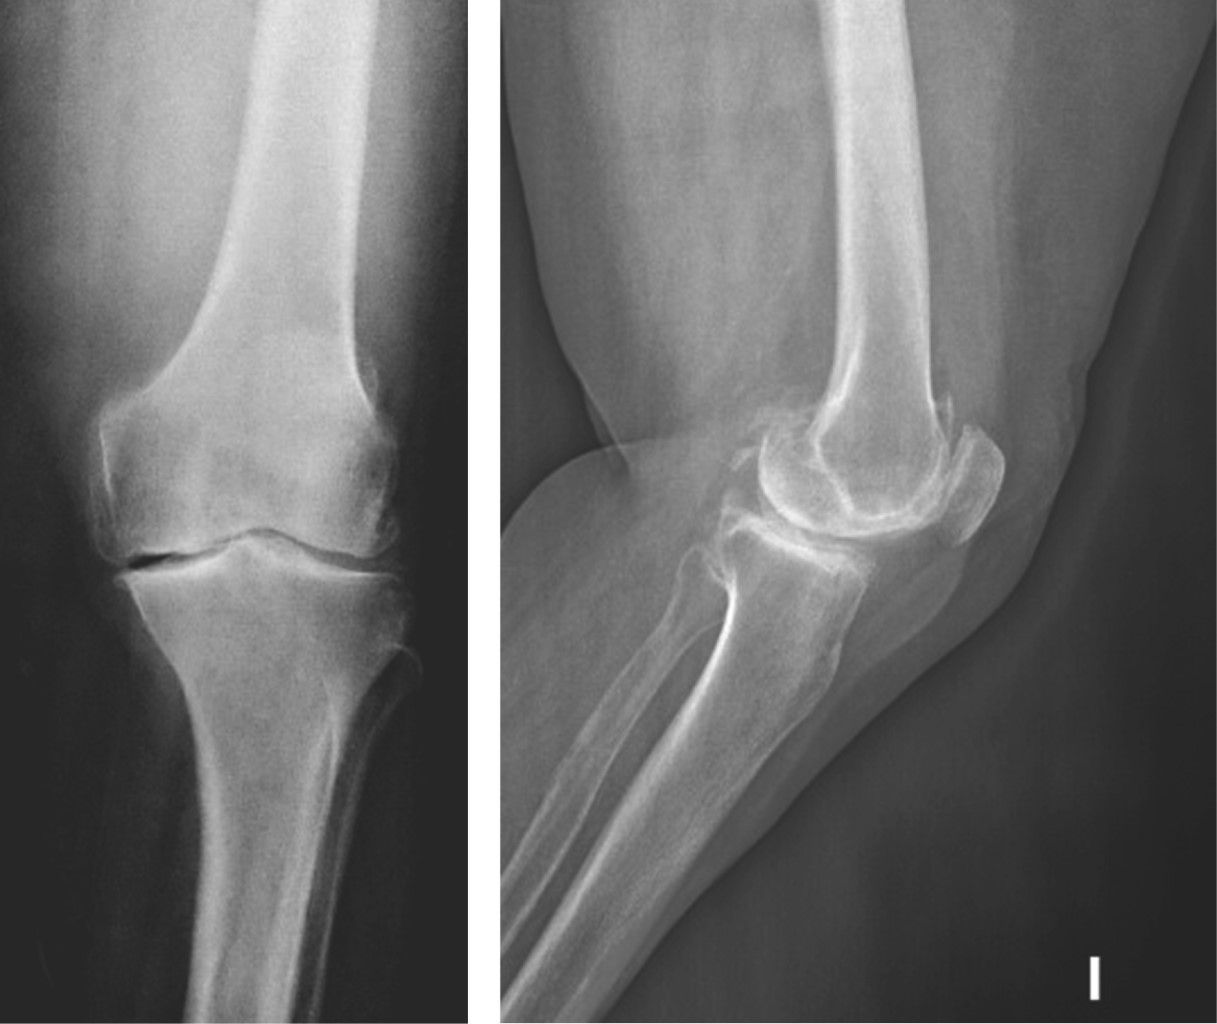

A su llegada a urgencias, se realizó un ultrasonido Doppler ante sospecha de TVP por presentar disnea de medianos que progresa a pequeños esfuerzos (Figura 1), en el cual se reporta: trombosis de la vena safena izquierda parcialmente canalizada, pantorrilla izquierda con imagen hipoecoica. Asimismo, por sospecha diagnóstica de tromboembolia pulmonar (TEP), se realizó angiotomografía axial computarizada de tórax en la que se reportó tromboembolia pulmonar segmentaria bilateral, por lo que se inició manejo con enoxaparina 60 mg subcutáneos cada 24 horas, así como furosemida 60 mg intravenosos dosis única. En la exploración física, se encontró una extremidad pélvica izquierda con aumento de volumen a nivel de rodilla y pierna hasta ambos maléolos y datos de insuficiencia venosa periférica. Dolor a la palpación sobre hueco poplíteo, línea articular medial y lateral de rodilla sin crépito óseo palpable. Arcos de movilidad de rodilla con flexión activa de 20°, flexión pasiva de 30°, limitadas por dolor sobre hueco poplíteo, línea articular medial y lateral. Fuerza de rodilla 4/5 de la escala de Daniels por dolor referido sobre hueco poplíteo, línea articular medial y lateral y debilidad. Sensibilidad conservada por dermatomas. Reflejos osteotendinosos patelar y aquíleo ++/++. Pulsos distales presentes. Llenado capilar inmediato. Se realizaron radiografías anteroposteriores con apoyo, lateral a 30° y axial a 45° de rodilla izquierda; se observa gonartrosis con presencia de disminución del espacio articular de predominio medial, esclerosis subcondral y osteofitos, además de edema de tejidos blandos (Figura 2). Se solicitaron estudios de laboratorio los cuales informaron los siguientes resultados: péptido natriurético cerebral (BNP) 128, glucosa 71, nitrógeno ureico en sangre (BUN) 16.3, creatinina 0.45, sodio 135, potasio 6.16, tiempo de protrombina (TP) 11.7, INR 1.04, dímero D 10,994, leucocitos 11.2, hemoglobina 11.1, examen general de orina: nitritos positivos, esterasa leucocitaria 250 leu/UI.

Figura 2